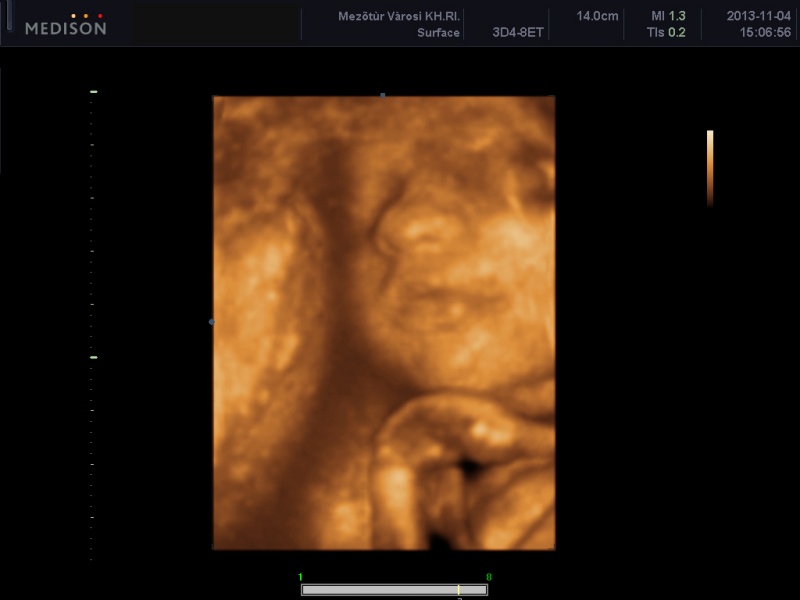

Én most 29 hetes vagyok, azaz holnap töltöm be. Nálam minden rendben van, ultrahangom 5 hete nem volt, de hétfőn megyünk 4D- re, már nagyon várom, mert még egyenlőre nem teljesen biztos hogy kislány, de majd remélem mostmár kiderül. A cukorterhelésem rendben volt, a vizeletemben nekem is volt baktérium, de nincs jelentősége, majd kedden újra megnézik.

Nagyon ficánkolós a picikém, a hidegfrontknál szinte szambázik a hasamban. Nos a hízásom is beindult már 7 kg plusszom van, szerintem ez még nem sok, mert igazából nem is látszik ratam csak a hatalmas pocim. A környezetemben aztmondják nagyobb a hasam mint kelene, na de nem baj az, lényeg hogy minden rendben legyen. Eléggé lent van a pocim, de gondolom ennek nincs jelentősége. Én még méreteket nem tudok hogy mekkora most a babám, na de majd hétfőn kiderül a 4D-n.